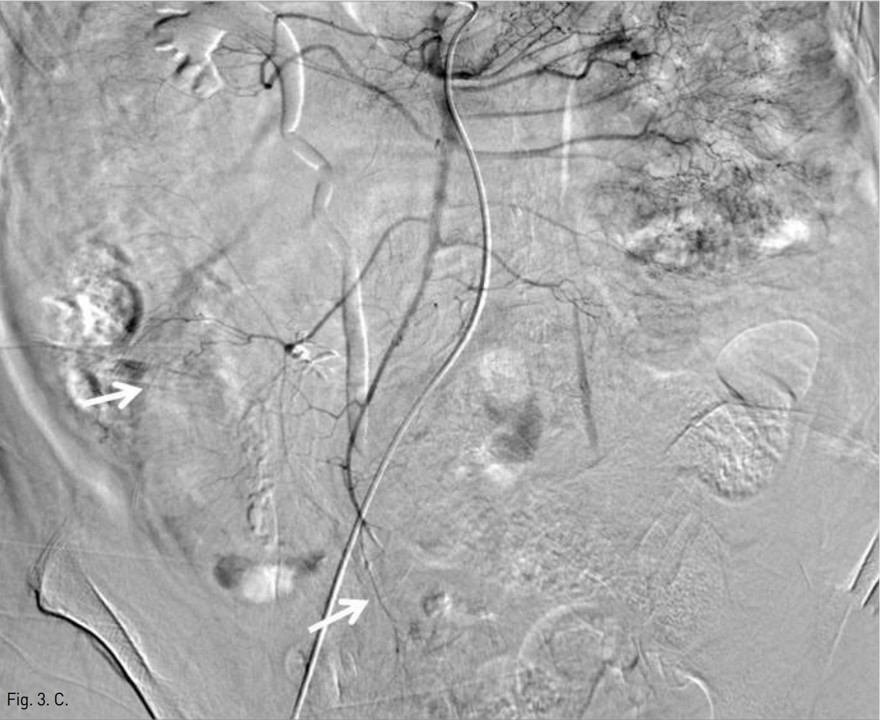

Fig. 3. C

Fig. 3C. Superior mesenteric angiogram after TAE demonstrates occlusion of the pseudoaneurysms with preserving blood supply to the affected bowels (arrows).